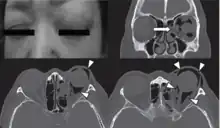

![]() | |

| Woman with preorbital swelling in orbital emphysema shown in CT scans | |